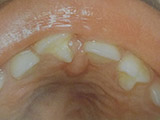

Υπενασβετίωση της αδαμαντίνης

Συνήθως εκδηλώνεται με λευκές, κίτρινες ή καφέ κηλίδες στους τομείς και τους γομφίους, μπορεί όμως να επηρεάσει και άλλα δόντια. Η κλινική εικόνα μπορεί να περιορίζεται μόνο στην εμφάνιση αυτών των κηλίδων, ή να είναι πιο σοβαρή προκαλώντας απώλεια της αδαμαντίνης του δοντιού, με συνέπεια την εμφάνιση ευαισθησίας και πόνου καθώς και τερηδόνας.

Η κατάσταση αυτή της αδαμαντίνης οφείλεται σε διαταραχή της διάπλασής της με αποτέλεσμα την ελλιπή ενσωμάτωση των μετάλλων στη δομή της. Έχουν ενοχοποιηθεί διάφοροι παράγοντες (περιβαλλοντικοί, ασθένειες της μητέρας και του βρέφους, διατροφή κ.ά.) οι οποίοι μπορούν να προκαλέσουν αυτές τις διαταραχές.